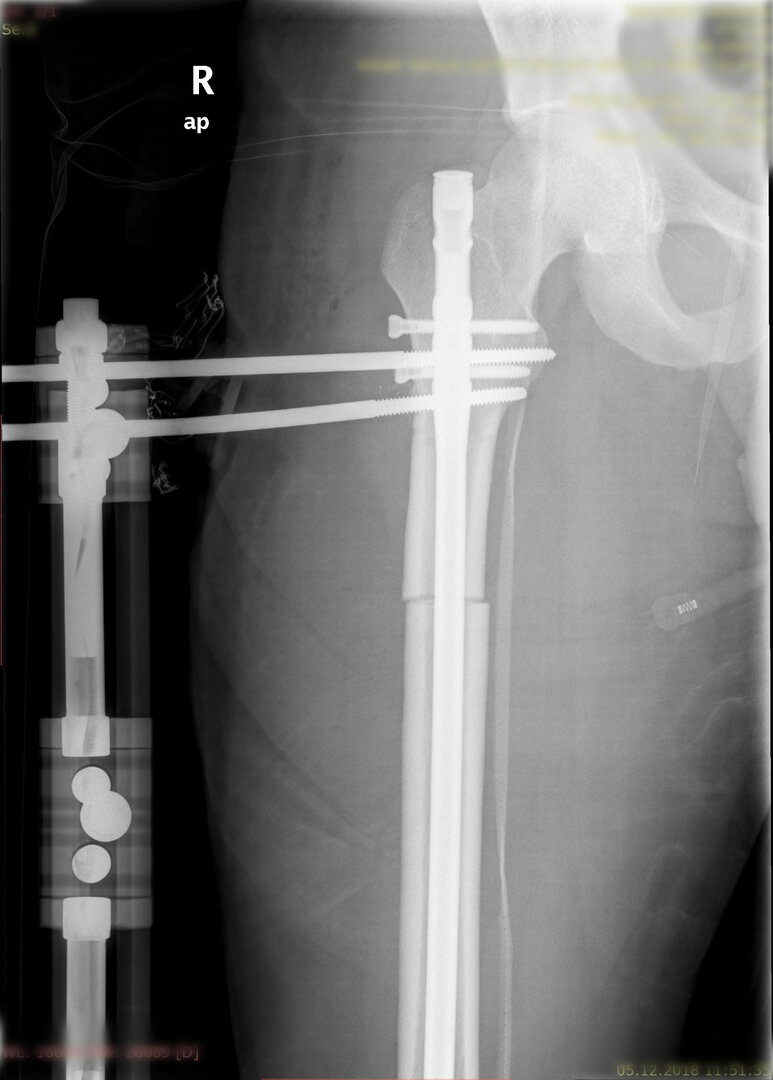

1. Kombine yöntem ile uzatma (LON-lengthening over nail- Çivi üzerinden uzatma):

Bu yöntemde uzatılacak kemiğin içerisine osteotomi sonrası bir intramedülller çivi yerleştirilir ve dışarıdan tek yönlü bir eksternal fiksatör kemiğe adapte edilir. Dışarıdan yine günde 4 defa çeyrek tur açarak 1 mm uzatma sağlanır. Uzatma miktarına ulaşılınca çivi kilitlenir ve uzayan bölümün sertleşmesi beklenir.

Görüntüleri büyütmek için üzerine tıklayınız.

Görseli büyütmek için üzerine tıklayınız. Görseli büyütmek için üzerine tıklayınız. Radyografi görseli büyütmek için üzerine tıklayınız. Radyografi görseli büyütmek için üzerine tıklayınız. Radyografi görseli büyütmek için üzerine tıklayınız.